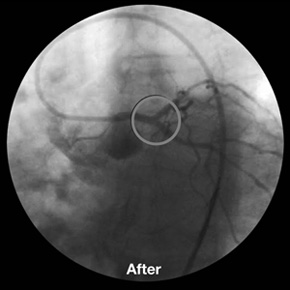

LMCA Y-Stenting with 3 BioDiamond stents.

9 x 3.5 mm distal LMCA,

9 x 3.0 mm ostial LAD and

9 x 3.0 mm ostial Cx.

CHP Beauregard, Marseille